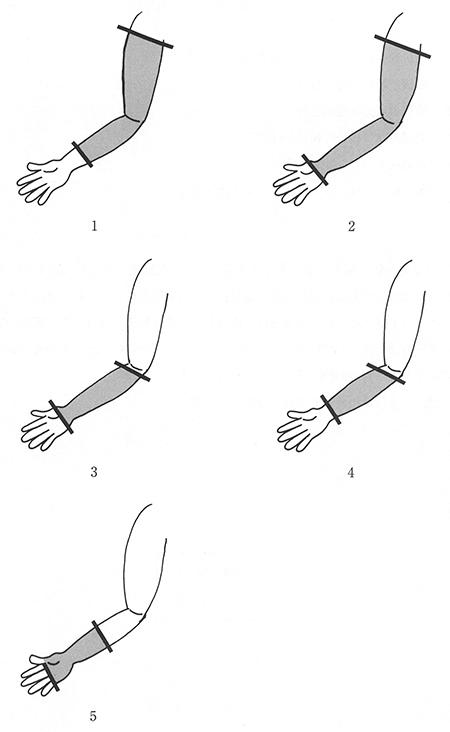

尺骨の骨幹部骨折での固定範囲で正しいのはどれか。

1

1

2

2

3

3

4

4

5

5